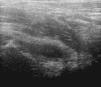

Las ecografías se realizaron por uno de los autores (RM, JGC) aunque las medidas que constan en el trabajo corresponden a RM, para garantizar igual metodología. Se efectuaron con el paciente en decúbito supino y el miembro inferior en extensión y posición neutra, colocando la sonda longitudinal y paralela al eje del cuello femoral. La distancia entre cuello del fémur y cápsula articular se valoró en mm en ambas caderas (sana y afectada) al comienzo y al final del episodio utilizando la escala de grises, la técnica Doppler no ha sido usada en el estudio. Las imágenes quedaron grabadas, para su posterior visión y valoración. Se utilizó un ecógrafo Logiq 5 (General Electric Medical System USA) y una sonda lineal de 12MHz.

La combinación de edad y fiebre, una vez confirmada la presencia de derrame articular (figs. 1 y 2) permitió el diagnóstico del 75% de los pacientes (tablas 2a y b). El criterio «mayor de 4 años sin historia de fiebre» mostró una especificidad y un valor predictivo positivo del 100% para el diagnóstico de ST. No hubo falsos positivos y 6 resultaron falsos negativos (3 por edad inferior a 4 años, por fiebre y otro por menor de 3 años y fiebre). El criterio «menor de 4 años e historia de fiebre» mostró una especificidad y un valor predictivo negativo del 95% para el diagnóstico de AS. Un caso fue falso negativo (la paciente de 11,7 años) y otro falso positivo (el menor de 3 años).

Respecto a la contribución de la ecografía, es importante señalar que la demostración de derrame articular, evita que traumatismos, infecciones o procesos en pelvis, columna u otro lugar de miembros inferiores se confundan con sinovitis de cadera, si se exceptúan las primeras horas del proceso, durante las que se han apreciado falsos negativos16. La ecografía no diferencia la AS de la ST y al parecer tampoco mejora su rentabilidad con power Doppler. Con esa técnica Strouse et al solo encontraron aumento de flujo en 3 de 11 casos con AS de cadera17. Dada la escasa sensibilidad y especificidad de la ecografía para diferenciar patologías, Bienvenu-Perrard et al concluyen que su principal ventaja radica en que un resultado negativo favorece la pronta realización de otras investigaciones diagnósticas18. A lo que se puede añadir, que un resultado ecográfico positivo, junto a unos pocos datos clínicos ayudan al diagnóstico diferencial.